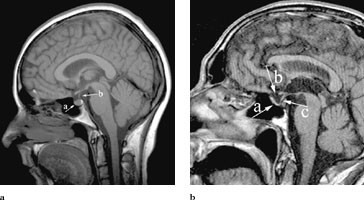

Det ble utført insulin-hypoglykemitest for å undersøke ACTH- og veksthormonsekresjonen nærmere og for å vurdere om det forelå hypotalamisk dysfunksjon. Pasienten hadde normal veksthormonrespons, men han hadde som forventet lav kortisol- og ACTH-respons (tab 2). MR viste en sella turcica som var normal i form og størrelse. Subaraknoidalrommet strakk seg i kaudal retning og omfattet store deler av sella turcica (fig 4a og b). Hypofysevev ble bare påvist i bunnen av sella. Bildet er forenlig med primær tom sella.

Tom sella er en anatomisk og radiologisk beskrivelse av en sella turcica som i varierende grad hernieres fra subaraknoidalrommet og cerebrospinalvæsken (2). Tom sella kalles primær når man ikke finner identifiserbar årsak og sekundær når det finnes en plausibel forklaring. Primær tom sella utvikles sannsynligvis på grunn av en ikke helt lukket diaphragma sellae. Trykk fra cerebrospinalvæsken påvirker innholdet i sella og medfører sammenpressing av hypofysen, som ofte kan sees som en tynn struktur i bunnen av sella (3). Om lag to tredeler av pasientene med primær tom sella har normal hypofysefunksjon, mens resten har tegn på endokrinologisk dysfunksjon.